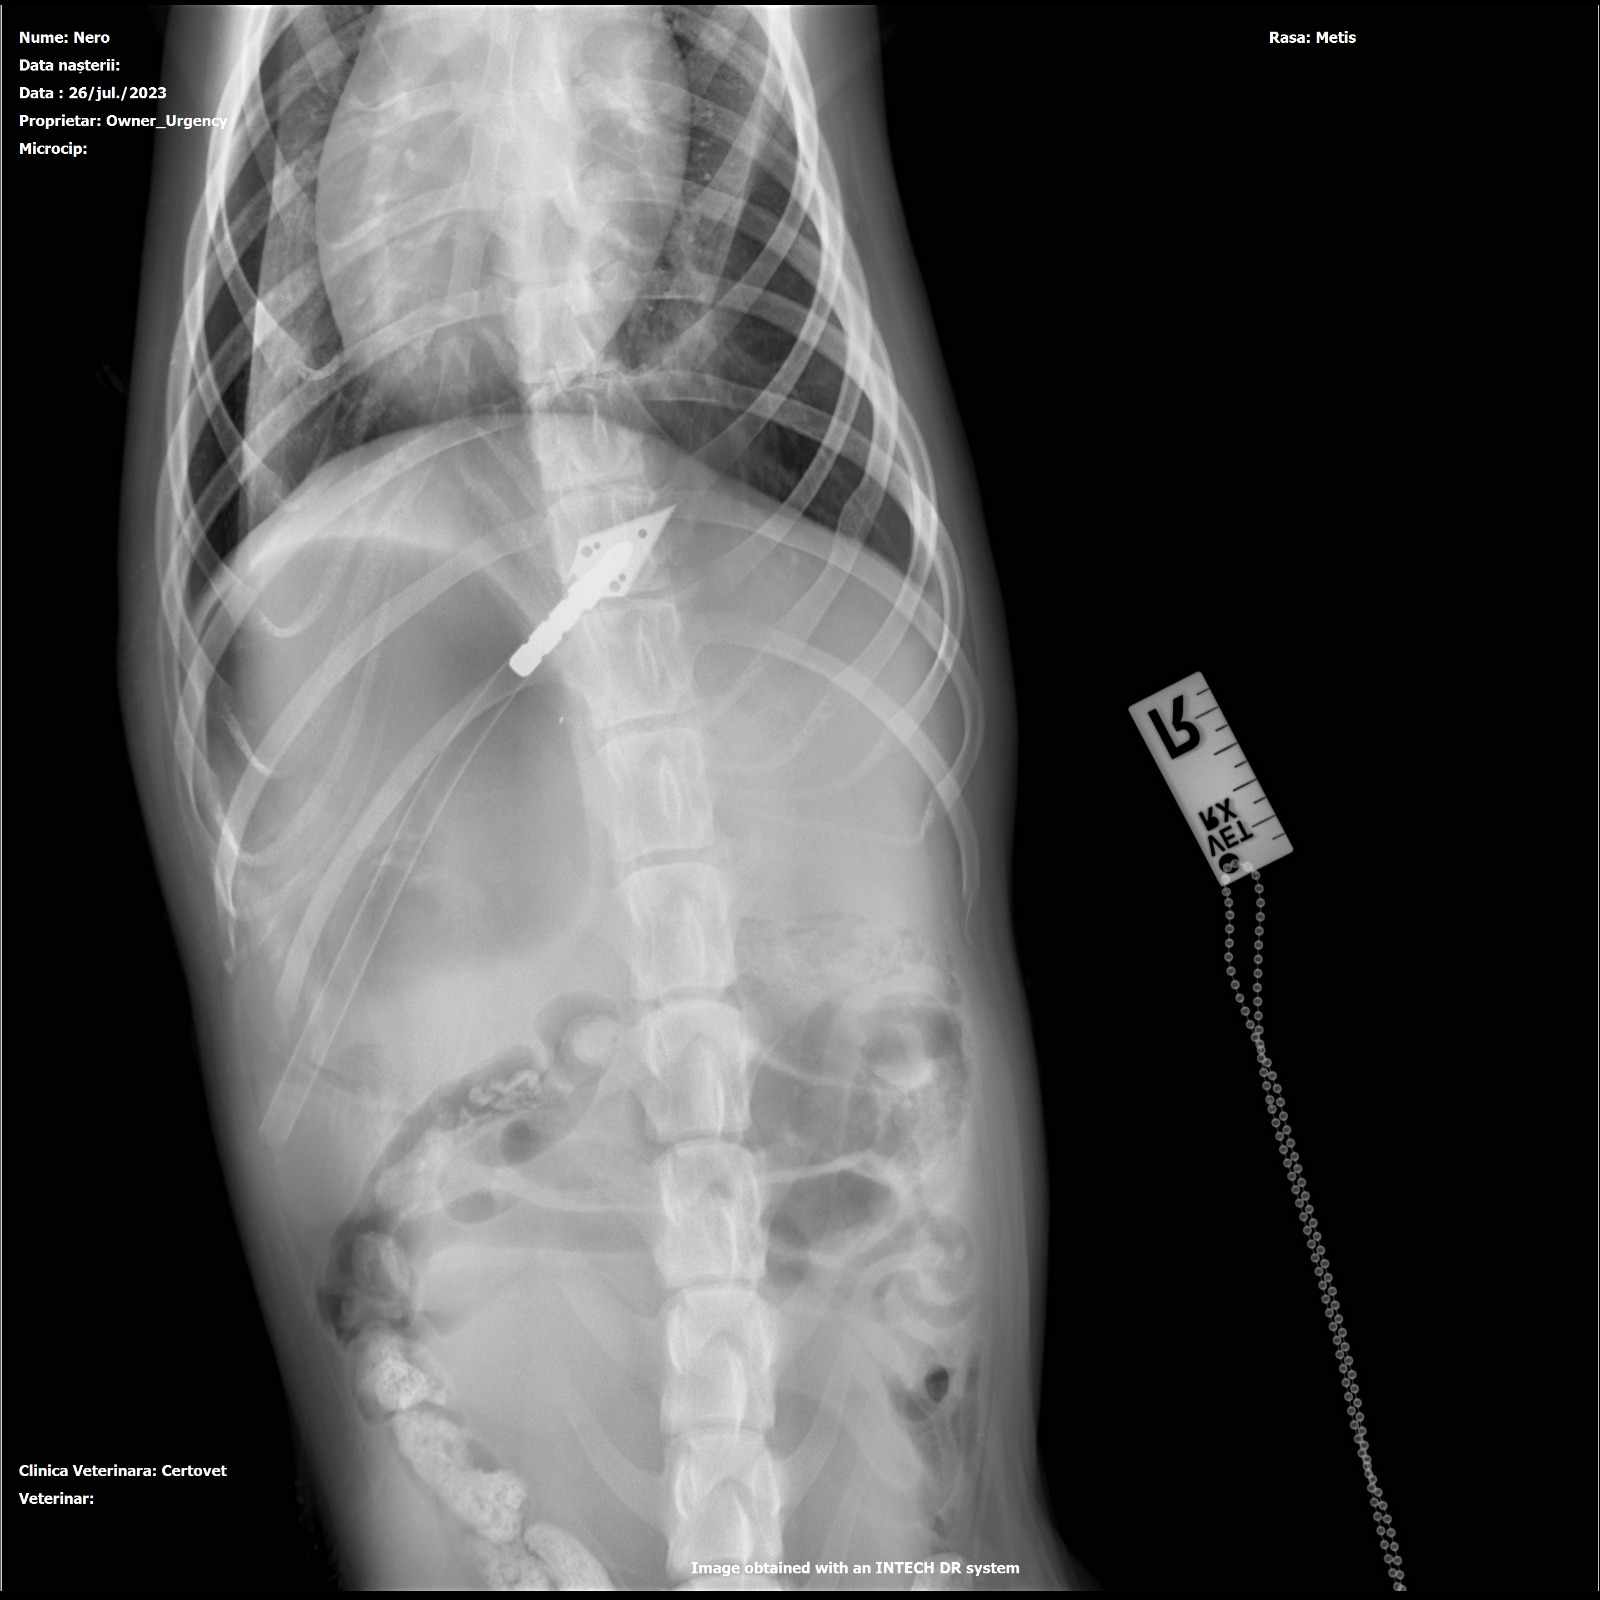

Gefunden wurde er im Sommer 2023 mit einem Pfeil in seinem Rücken, irgendeine abartige Kreatur hat versucht, den wehrlosen jungen Straßenhund zu töten!! (siehe Bilder)

Die Ärzte, die ihm den Pfeil rausoperierten, prognostizierten, dass er nie wieder würde laufen können, zu nah steckte der Pfeil an der Wirbelsäule…doch dann das Wunder: mithilfe von tollen Spendern konnten nicht nur die Kosten der OP sondern auch für einen Rolli gestemmt werden.